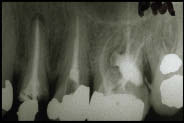

Seeking dentists’ help with unidentified woman

The American Dental Association

The National Center for Missing & Exploited Children is asking for dentists’ help in identifying a woman found near an abandoned farm in 2008. The center released X-rays of the woman’s teeth, photographic and sketch facial composites created by forensic artists of what the woman may have looked like in real life and a photo … Read more